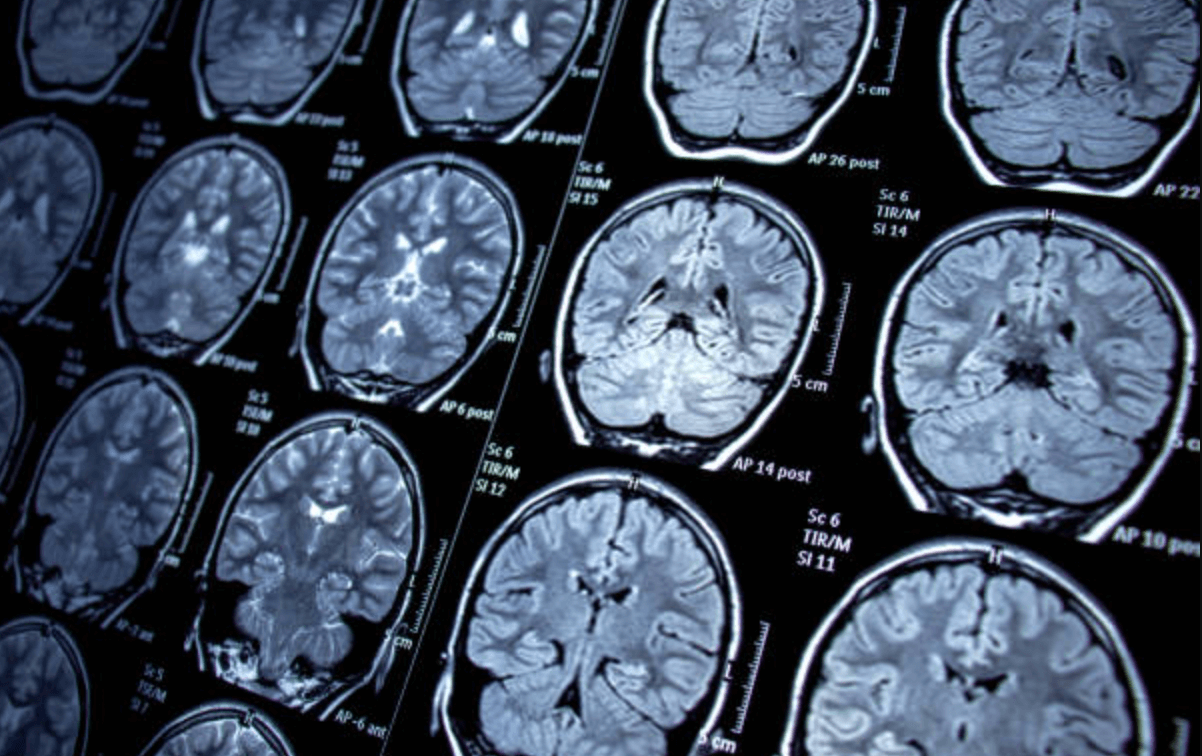

MRI를 찍는 이유는 따로 있습니다. 물론 보다 정확한 정보를 얻기 위함이지만, 자기 공명영상(MRI)은 자석과 전자기파를 사용하여 인체 내부의 세부적인 영상을 찍는 영상 진단법입니다.

MRI는 CT촬영보다 해상도가 높고 조직도가 우수하여, 뇌, 척추, 관절, 근육, 혈관 등의 질환을 진단하는데 널리 사용되고 있는 촬영법 입니다. MRI를 찍는 진짜이유는 아래와 같습니다.

- CT보다 해상도가 높다

- 질병을 더 정확하게 진단

- 방사선에 노출되지 않는다

- 영상을 여러 방향으로 확인가능하다

- CT보다 검사 기간이 짧다

- 폐소공포증 환자도 검사를 받을 수 있다

MRI를 찍는 진짜 이유는 고가이지만, 질병을 더욱더 정확하게 진단이 가능하며, 방사선 노출이 되지 않는 것이 MRI를 찍는 진짜 이유가 아닐까 생각합니다. 이상으로 MRI 보험적용 가격 검사 비용 포스팅을 줄입니다.